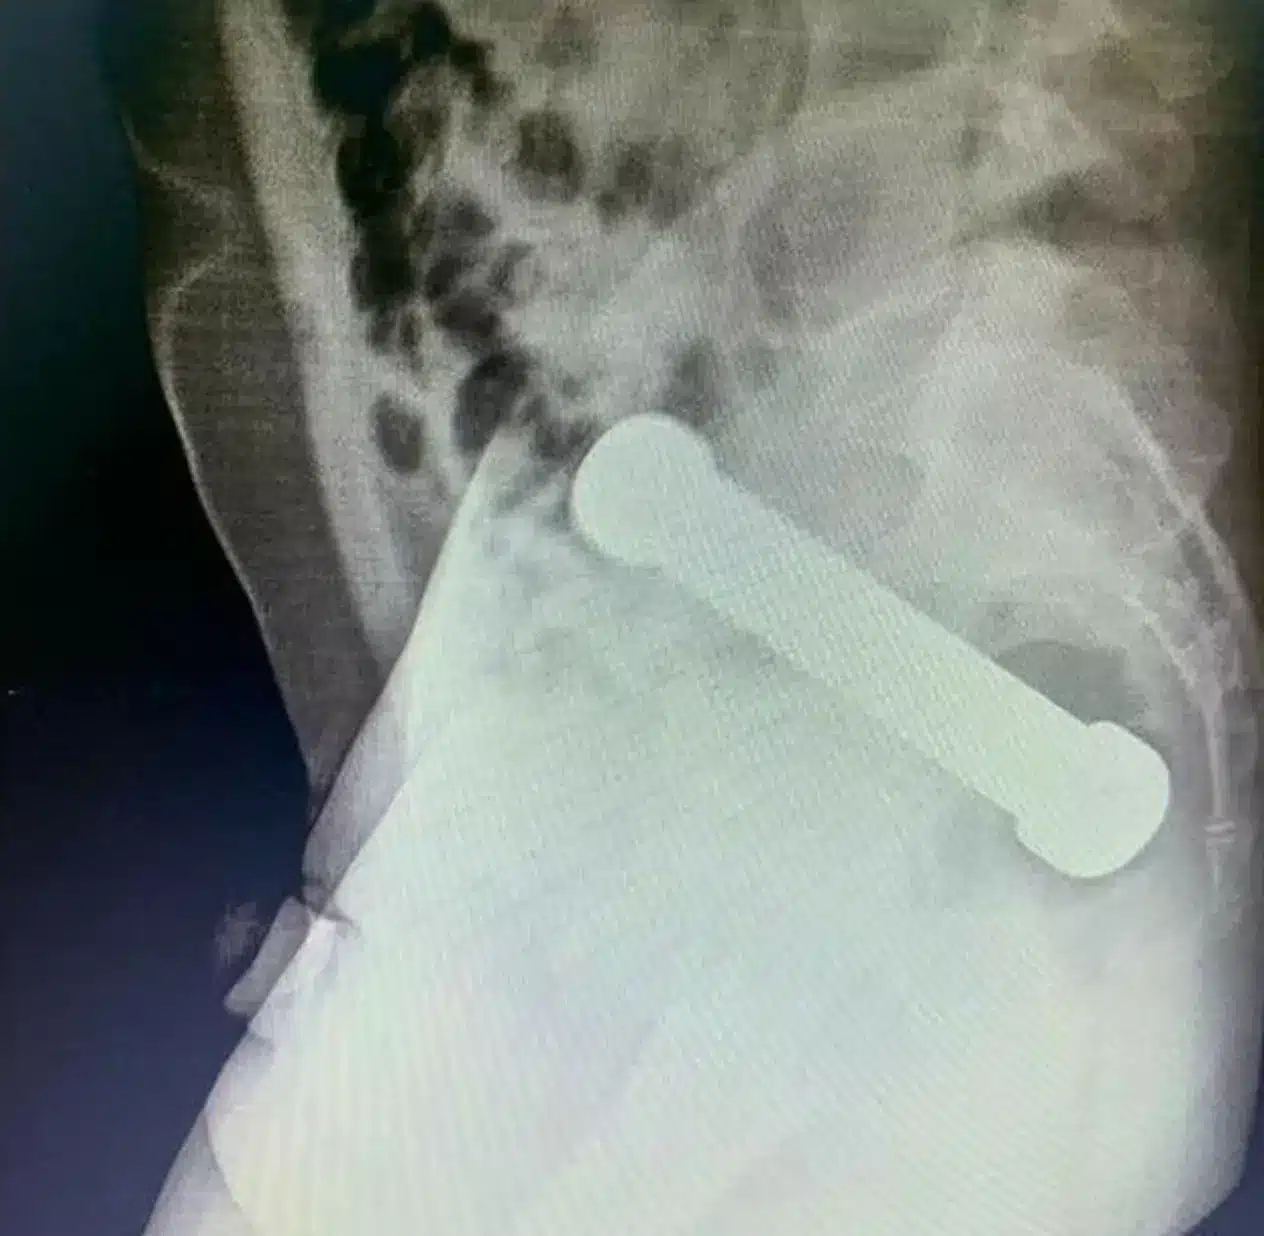

เคสสุดตะลึง ชายชาวบราซิลวัย 54 ปี ทนทุกข์ 2 วันก่อนมาโรงพยาบาลด้วยอาการปวดท้องรุนแรง ผลเอ็กซเรย์พบดัมเบลยาว 20 ซม. หนัก 2 กิโลกรัม ติดคาลำไส้ แพทย์ต้องใช้วิธีพิเศษ ใช้มือล้วงเข้าไปนำออกมา

ผลการเอ็กซเรย์เผยให้เห็นดัมเบลขนาดความยาว 20 เซนติเมตร ติดค้างอยู่บริเวณรอยต่อระหว่างลำไส้ใหญ่กับทวารหนัก บทความในวารสารการแพทย์ International Journal of Surgery Case Reports ระบุว่า กรณีนี้มีเหตุจูงใจทางเพศ ซึ่งผู้ป่วยมักไม่ค่อยเปิดเผยรายละเอียดทั้งหมด